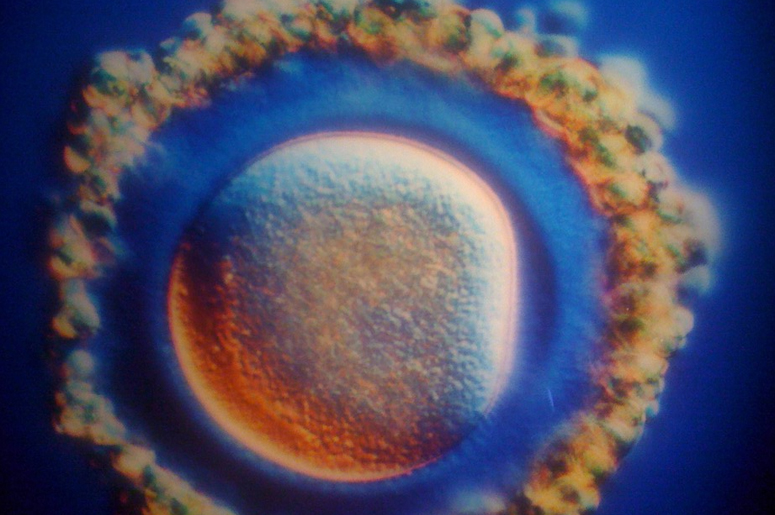

Зарождение жизни: Фотографии Леннарта Нильсона